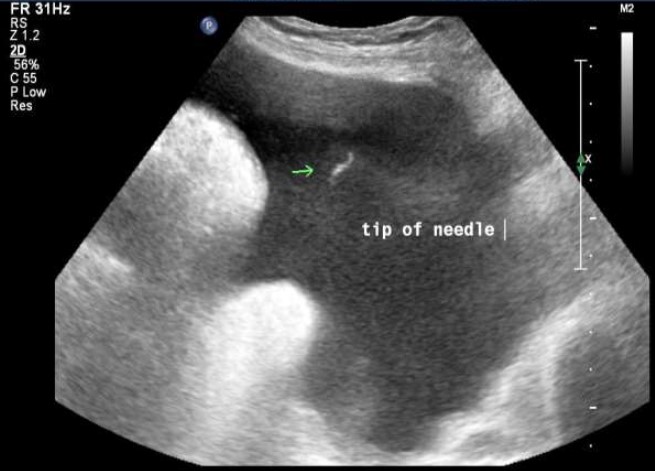

Procedural Guidance

The use of ultrasound to guide procedures such as vascular access, lumbar puncture, pericardiocentesis, paracentesis, thoracentesis, and nerve blocks enhances accuracy, reduces associated procedural complications, and improves patient safety.